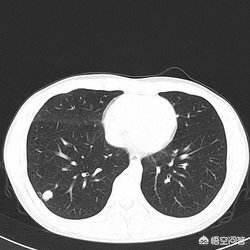

肺结节通俗的讲就是CT上黑色的肺里有小白点。直径大于3cm一般称为肺部肿块,肺癌的可能性相对较大。通常我们将直接小于3cm的圆形或者椭圆形占位病变称之为孤立性肺结节,它被肺实质包围,完全没有相关的淋巴结肿大、肺不张或肺炎。直接小于2cm的称为肺内小结节,直接小于5mm的称为微小结节。

如何判断肺结节是良性还是恶性呢?1.结节的位置:肺癌更多发生于上叶,尤其好发于右肺,但肺结核留下的一些疤痕结节也饿多发于上肺,所以要注意鉴别。2.结节的形态:胸部ct被公认为是鉴别肺部小结节良恶性的最佳检查手段。假如CT上描述有深分叶、短粗毛刺、空泡征、空气支气管征、胸膜凹陷征、肺血管集中征以及明显的强化征等,都认为是恶性征象,千万不可懈怠。如果结节边界光滑,钙化位于病灶中央或为层状、弥漫性和爆米花样则多见于良性病变,结节内有脂肪多见于良性的错构瘤等。3.结节的大小:直径小于5mm,恶性的可能性很小,大约在1%以内;5~10mm时,恶性可能性为6%—28%;直径大于20mm的肺结节恶性概率达到80%。